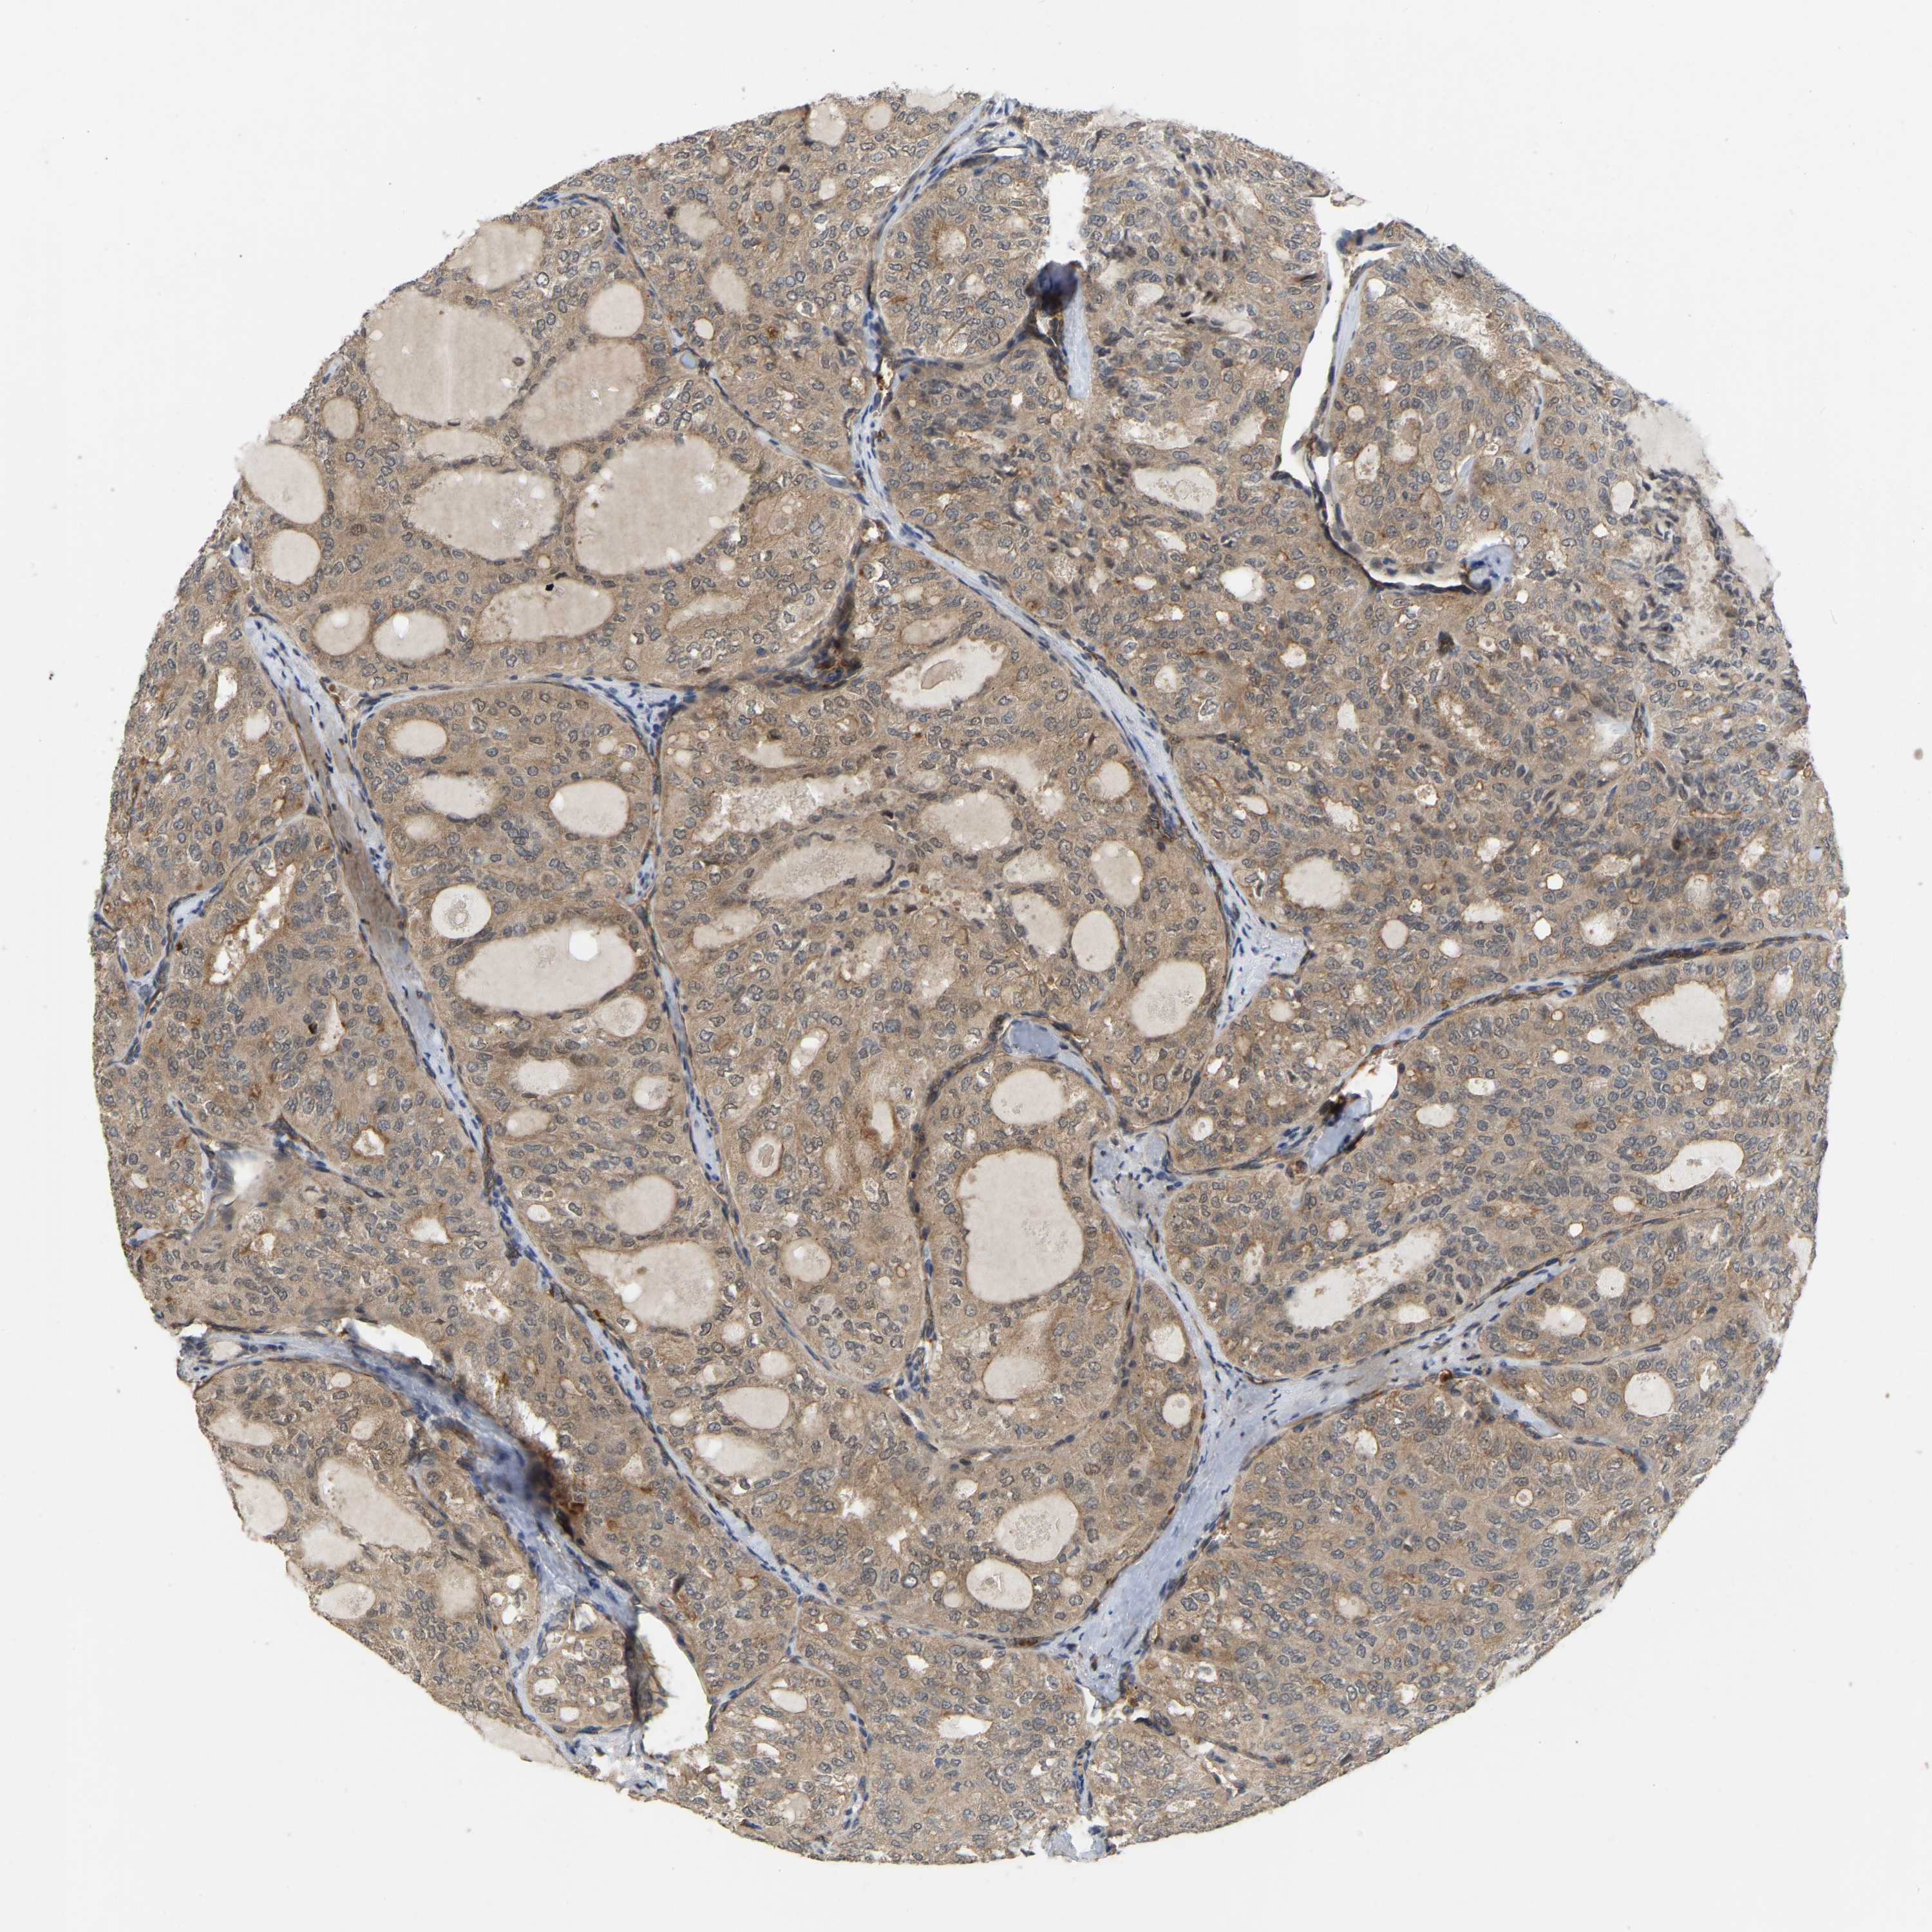

THYROID CANCER - Protein expressioni

A mouse-over function shows sample information and annotation data. Click on an image to view it in a full screen mode. Samples can be filtered based on level of antibody staining by selecting one or several of the following categories: high, medium, low and not detected. The assay and annotation is described here.

Note that samples used for immunohistochemistry by the Human Protein Atlas do not correspond to samples in the TCGA dataset.

Antibody stainingi

Antibody staining in the annotated cell types in the current human tissue is reported as not detected, low, medium, or high, based on conventional immunohistochemistry profiling in selected tissues. This score is based on the combination of the staining intensity and fraction of stained cells.

Each image is clickable and will lead to virtual microscopy that enables deeper exploration of all samples and also displays staining intensity scores, fraction scores and subcellular localization as well as patient and tissue information for each sample.

Antibody HPA008183

Antibody HPA053882

Antibody CAB019313

Staining

High

Medium

Low

Not detected

Intensity

Strong

Moderate

Weak

Negative

Quantity

>75%

75%-25%

<25%

None

Location

Nuclear

Cytoplasmic/membranous

Cytoplasmic/membranous,nuclear

Papillary adenocarcinoma, NOS

Follicular adenoma carcinoma, NOS